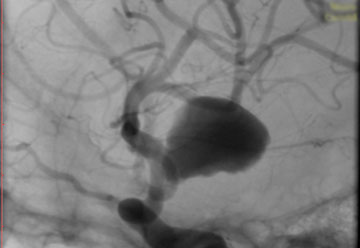

La paciente ingreso al Servicio de Hemodinamia el día martes 11 de febrero con un aneurisma cerebral gigante en la carótida izquierda y se le practicó una embolización; es decir una oclusión por dentro del mismo, donde se colocó un dispositivo denominado coils más un stent diversor de flujo. El procedimiento fue exitoso y contó con la colaboración de médicos neurointervencionistas del Instituto Oulton de la Ciudad de Córdoba.

La paciente llevaba un tiempo refiriendo dolores de cabeza, trastornos visuales por lo cual luego de realizarcele los estudios pertinentes y comprobar la patología se programó el procedimiento. Debido a que el Hospital Vera Barros no contaba con la tecnología necesaria para esta práctica compleja es que se realizó en la nueva Sala de Hemodinamia de INCOR en el marco de un convenio de trabajo conjunto entre la salud pública y la privada.